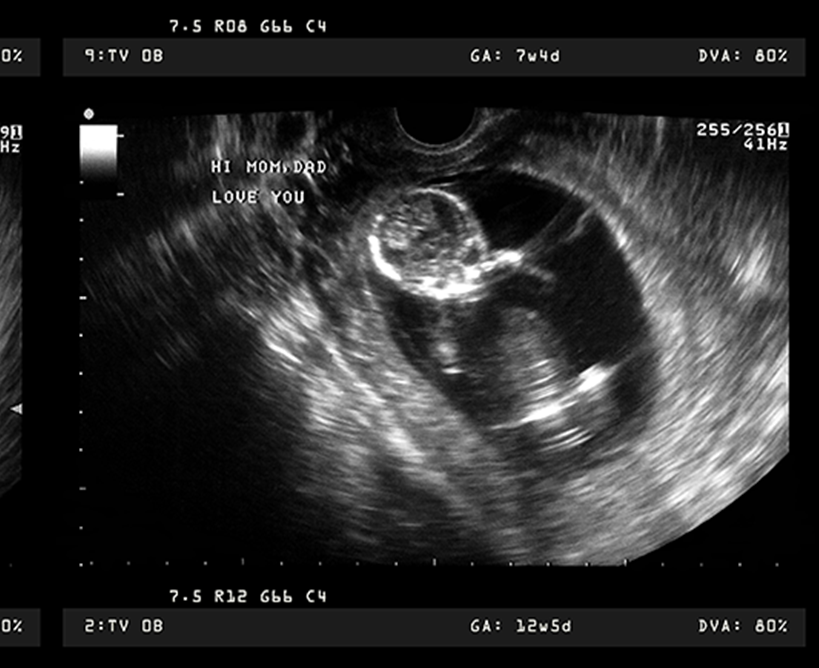

¡Ya estás en el tercer trimestre del embarazo! ¡Es la recta final! Seguramente notas lo mucho que ha crecido tu bebé es en el tamaño que tiene tu panza.

Este trimestre es muy importante por estar lleno de avances en el desarrollo del pequeño y la maduración de algunos órganos. Por ejemplo, durante el tercer trimestre, el feto sigue creciendo en tamaño y peso, además de comienza a posicionarse cabeza abajo.

Falta muy poco para que el feto alcance la medida de 49 a 53 cm y pesa cerca de 4 kilos. Lo más destacable en este trimestre es que: